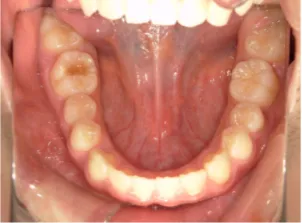

治療中④小2(8y2m)~小3(9y1m):QHとBHで拡大・アーチ形態の修正、ブラケットで前歯の並べ替えまで終了

| 行ったご提案・診断内容 | 成長期に行う治療と咬合治療をご提案 受け口用ファンクショナルアプライアンス(写真②③)からスタートし、小2以降で上下顎の拡大・歯列弓の形態修正・前歯の並べ直し(写真④)を行いその後、モノブロック(筋機能的咬合誘導)装置(写真⑤)へ移行し、受け口の再発予防と永久歯を適切な咬み合わせに誘導し、必要によりマルチブラケット法へ移行する治療方法を提案しました。 成長期治療(成長時期にお口の環境を整える治療) 2年生以降から 咬合治療 |

| 治療期間 | 12か月:受け口用ファンクショナルアプライアンス(写真②③) 12カ月:成長期治療の動的治療期間(写真④) 現在、成長の経過観察と咬合誘導中です(写真⑤~⑨) |